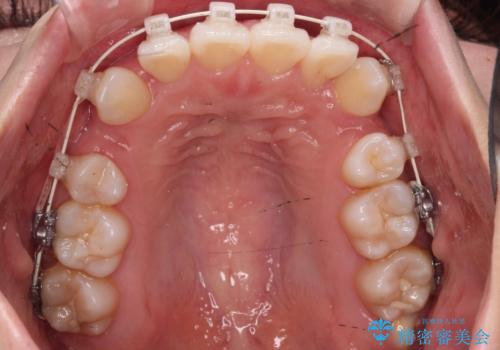

- 矯正装置

- 審美装置

凸凹を治すために、上下左右の小臼歯を抜歯してワイヤー矯正を行いました。

患者様には、顎間ゴムを使用していただくことで、2年という期間で治療を終了することができました。